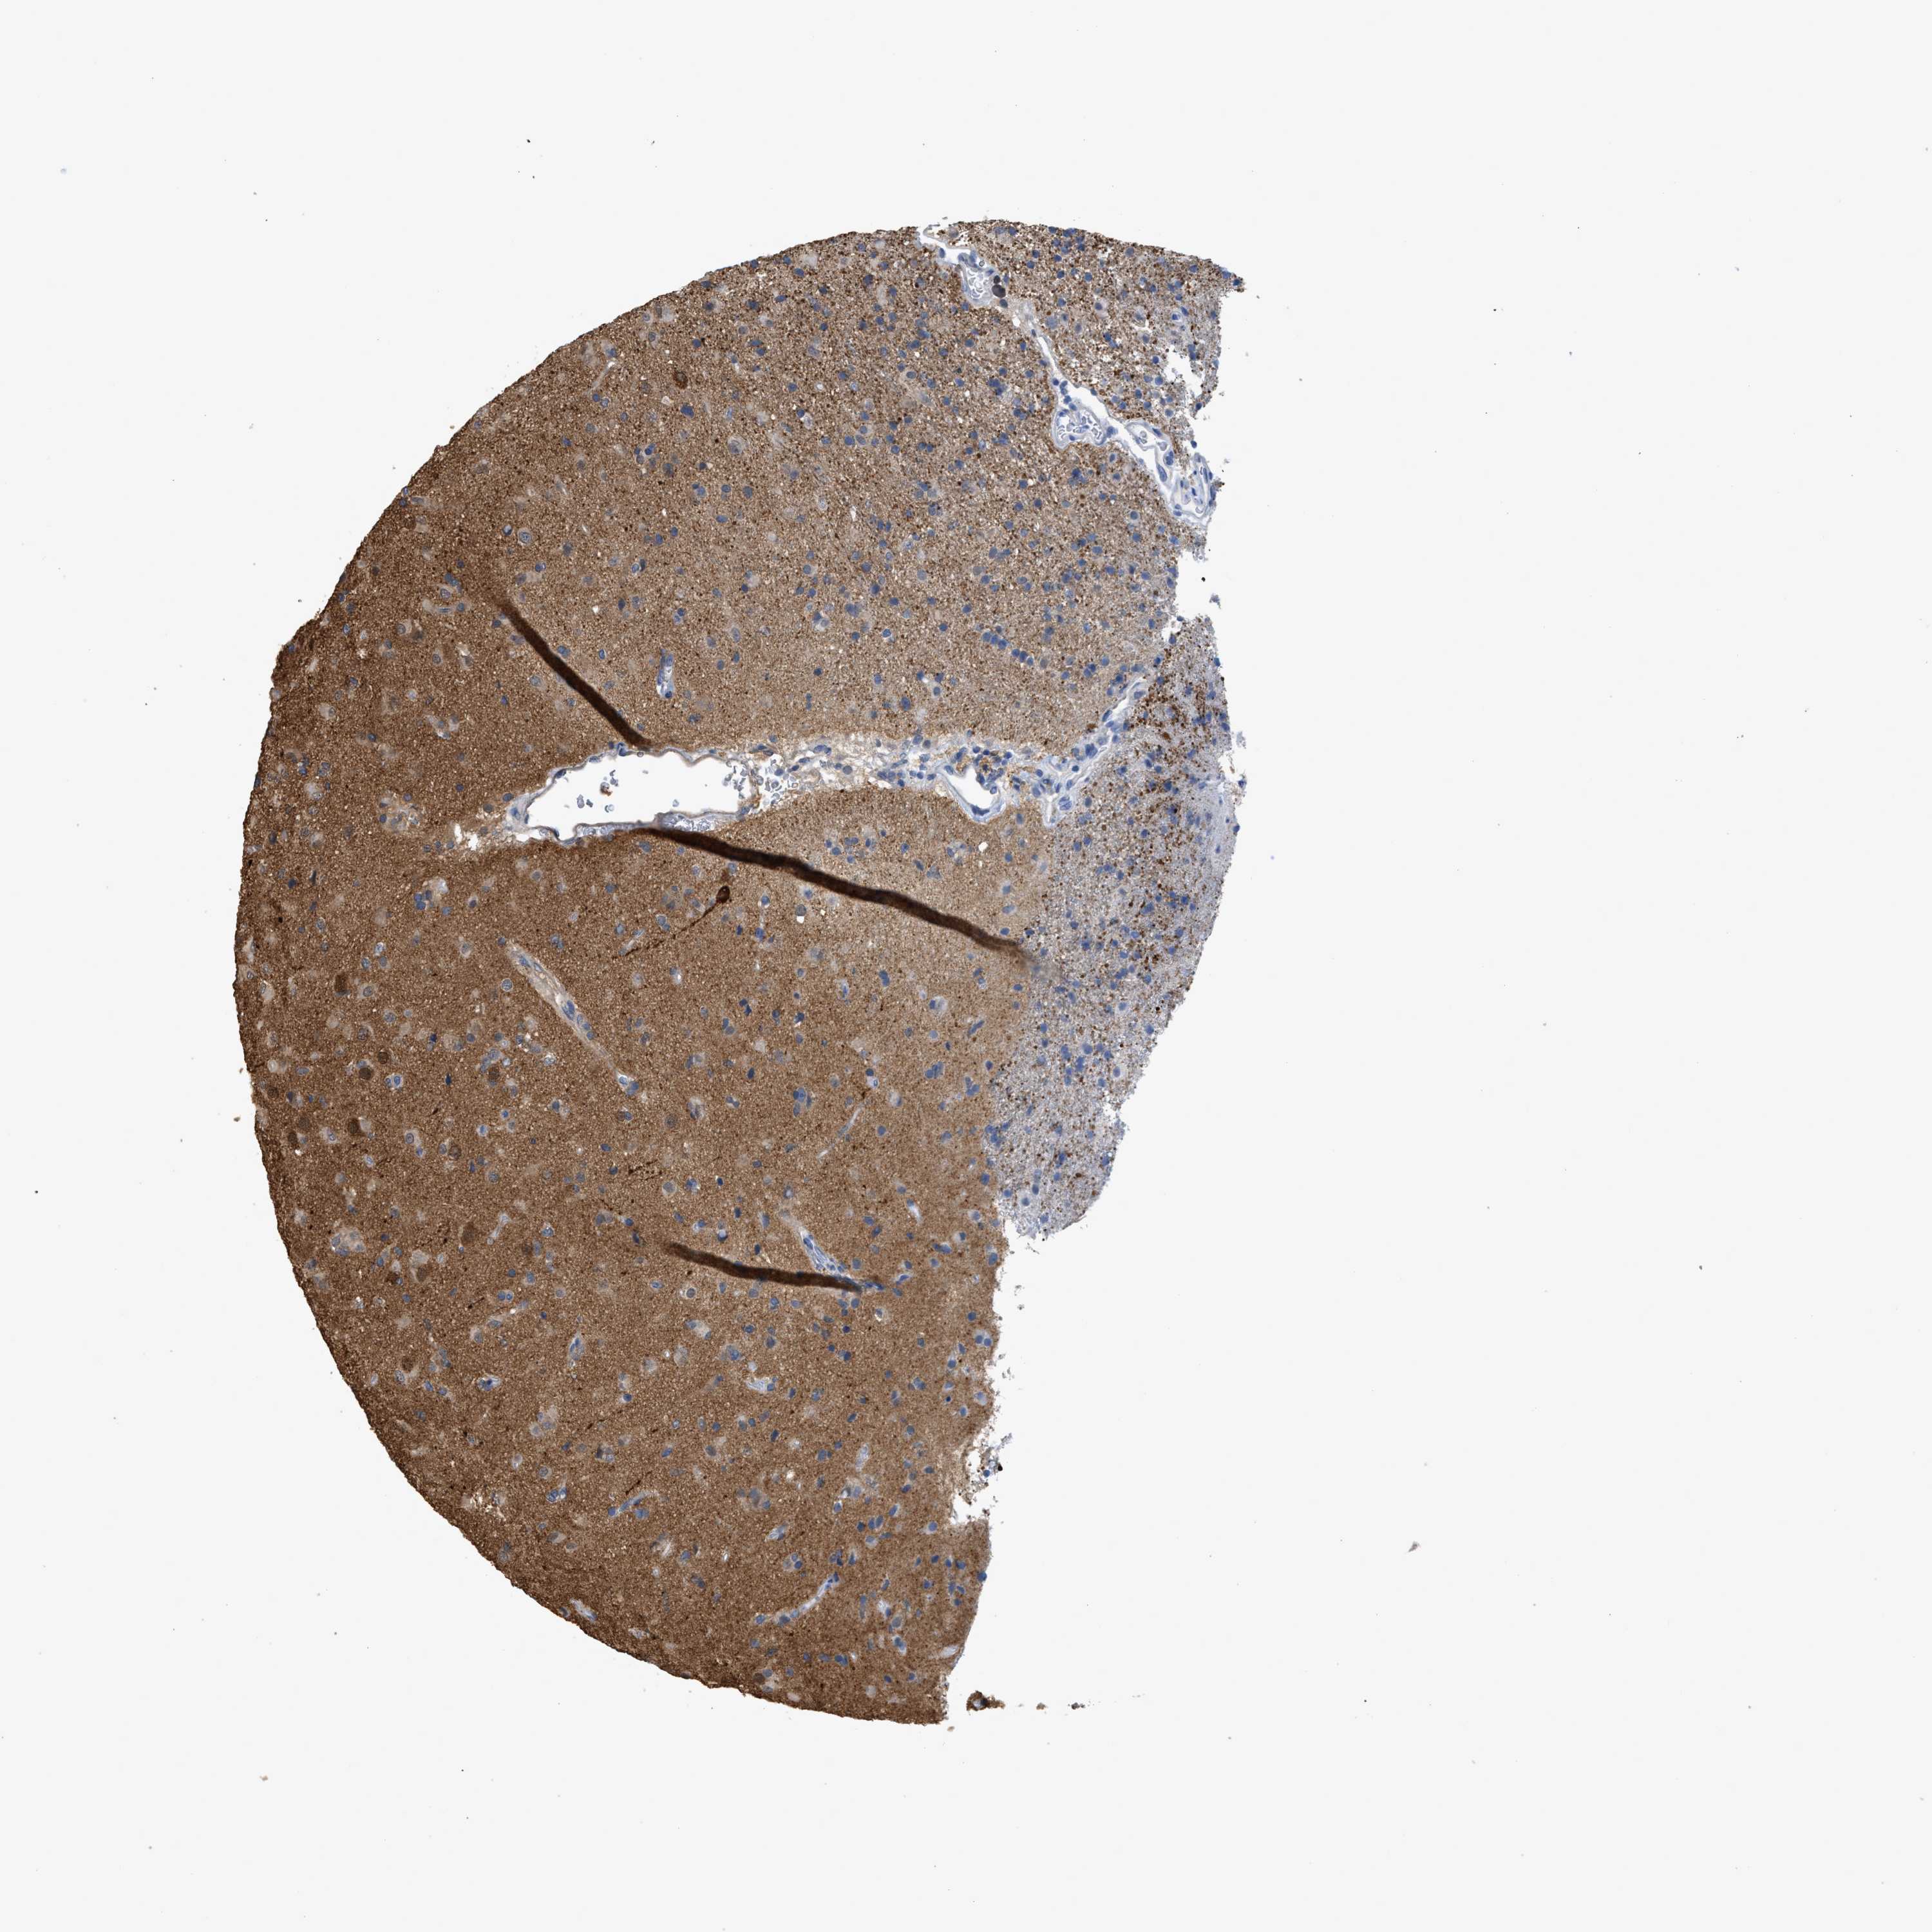

GLIOMA - Protein expressioni

A mouse-over function shows sample information and annotation data. Click on an image to view it in a full screen mode. Samples can be filtered based on level of antibody staining by selecting one or several of the following categories: high, medium, low and not detected. The assay and annotation is described here.

Note that samples used for immunohistochemistry by the Human Protein Atlas do not correspond to samples in the TCGA dataset.

Antibody stainingi

Antibody staining in the annotated cell types in the current human tissue is reported as not detected, low, medium, or high, based on conventional immunohistochemistry profiling in selected tissues. This score is based on the combination of the staining intensity and fraction of stained cells.

Each image is clickable and will lead to virtual microscopy that enables deeper exploration of all samples and also displays staining intensity scores, fraction scores and subcellular localization as well as patient and tissue information for each sample.

Antibody HPA019086

Antibody HPA030619

Staining

High

Medium

Low

Not detected

Intensity

Strong

Moderate

Weak

Negative

Quantity

>75%

75%-25%

<25%

None

Location

Nuclear

Cytoplasmic/membranous

Cytoplasmic/membranous,nuclear

Glioma, malignant, High grade

Glioma, malignant, Low grade